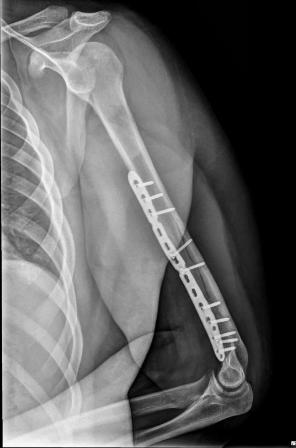

術(shù)中,醫(yī)生通過精細(xì)操作,將骨折端完美復(fù)位,并用鋼板螺釘牢固固定,為骨骼愈合提供了穩(wěn)定的力學(xué)環(huán)境。術(shù)后小王恢復(fù)順利,手臂屈伸活動(dòng)自如,目前已進(jìn)入康復(fù)階段。小王和家人對治療效果非常滿意,連連稱贊:“沒想到掰個(gè)手腕會(huì)骨折,更沒想到恢復(fù)得這么好,真是太感謝醫(yī)生了!”

鋼板固定手術(shù)治療后X光片,術(shù)后恢復(fù)良好